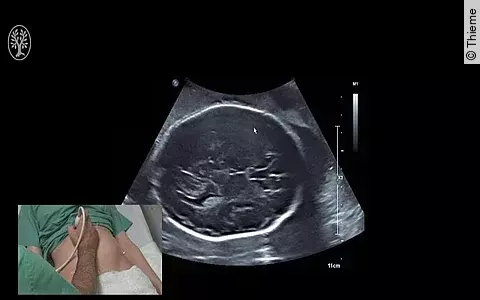

Nehmen Schwangere die Bewegungen ihres Kindes im Mutterleib weniger wahr, wird dies nicht immer ernstgenommen und überprüft. Dabei ist das Risiko für schwere Komplikationen hoch und eine schnelle Abklärung notwendig.

Für Sie operierte PD Dr. Markus Hoopmann aus dem Department für Frauengesundheit Tübingen. Es moderierten: Prof. Dr. Bernhard Krämer und OA Dr. Felix Neis.